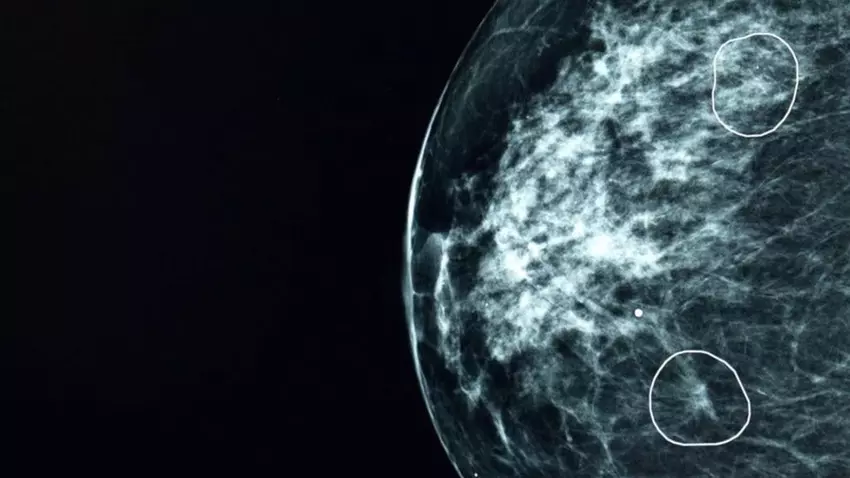

Podczas testów w brytyjskiej Narodowej Służbie Zdrowia (NHS), narzędzie sztucznej inteligencji o nazwie Mia z powodzeniem zidentyfikowało oznaki raka piersi u 11 kobiet, które zostały początkowo przeoczone przez lekarzy podczas analizy mammografii.

Podczas badania ponad 10 000 skanów piersi, Mia poprawnie zidentyfikowała wszystkie nowotwory wykryte przez lekarzy, a dodatkowo wskazała 11 pacjentek z niewielkimi guzami mierzącymi około 6 mm. Na tak wczesnym etapie rak jest często trudny do wykrycia gołym okiem.